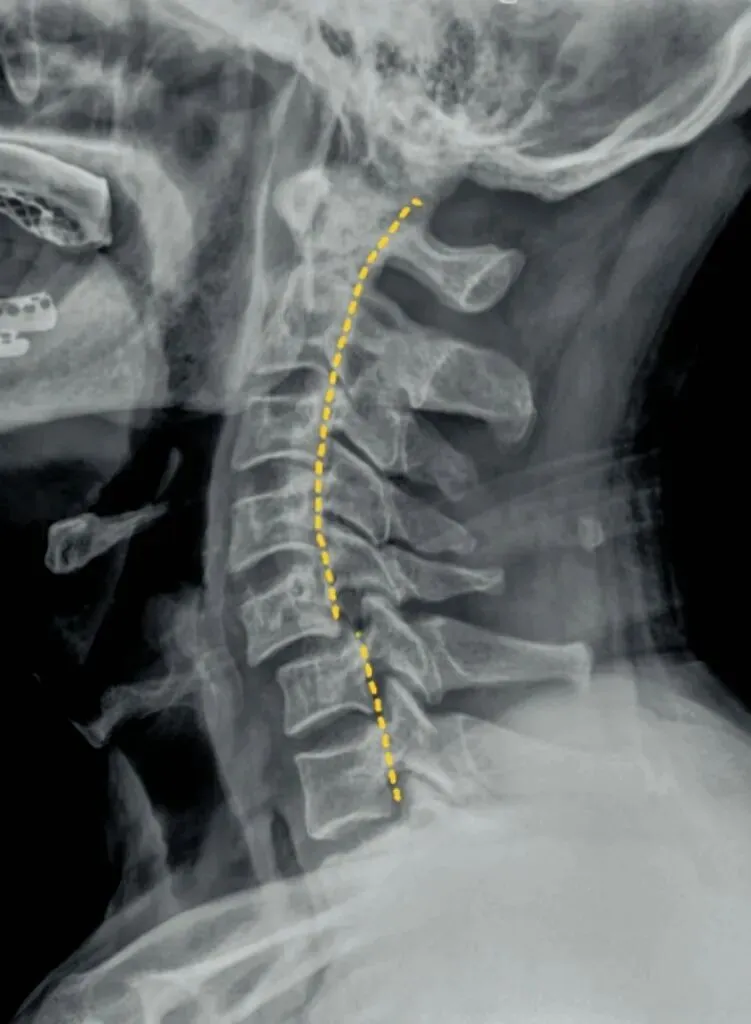

七滑脱是指颈椎椎体的滑脱,以下位椎体分为四等份,以此判断上位椎体向前或者向后的滑脱程度,

也是我们所说的椎体序列不整齐,椎体后缘的平滑曲线出现台阶或错位,多发生在颈三和颈4椎体。

颈椎滑脱是颈椎不稳的结局,颈椎不稳多因椎间盘和关节突关节退变及关节活动度过多和过大所致。正常的颈椎侧位片只是能看到静态下的椎体滑脱,有的病人在做前屈和后伸活动时才出现滑脱,因此需做颈椎的过伸和过屈动力位侧位片检查来判断不稳。